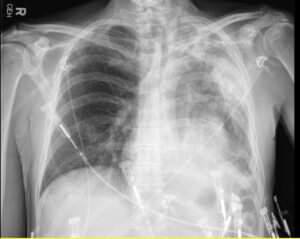

A 52-year old man with a history of diffuse large B cell lymphoma in remission presented with 3 weeks of shortness of breath, cough, fever, and shock. Electrocardiogram revealed sinus tachycardia, diffuse ST segment elevations, PR segment depression, prolonged QTc, and electrical alternans. Bedside echocardiogram was performed, revealing a large circumferential pericardial effusion with tamponade physiology. The patient underwent echo-guided pericardiocentesis with drainage of 400 ml of purulent fluid. Pericardial and blood cultures were positive for Haemophilus influenzae. A CT of the chest was indicative of empyema. Given the patient’s history of rituximab use, autologous stem cell transplant, and profound infection, immunoglobulin levels were drawn and found to be undetectable. The patient received 6 weeks of intravenous antibiotics with IVIG infusions. He was treated with colchicine and aspirin for purulent pericarditis. Two months later, a cardiac MRI was performed, which revealed resolution of the pericardial effusion. No evidence of constrictive pericarditis was noted on MRI, but continued pericardial enhancement was observed. Colchicine was continued for an additional 3 months. The patient made a full recovery at 6 month follow up.